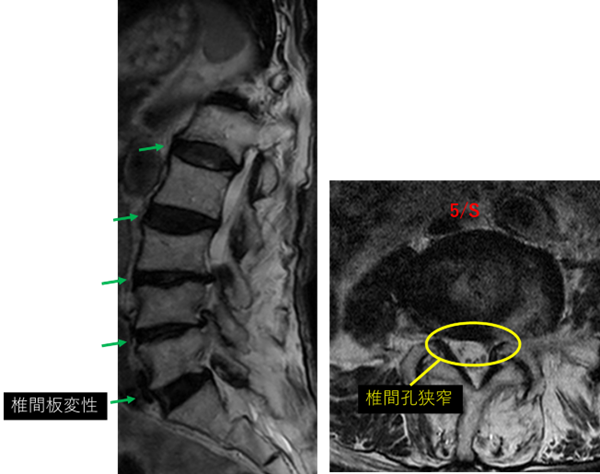

L1/2: 変性、膨隆、右椎間孔狭窄

L2/3: 変性、膨隆

L3/4: 変性、膨隆、左椎間孔狭窄

L4/5: 変性、膨隆、左椎間孔狭窄

L5/S: 変性

以上の事が画像上認められます。

L1/2、2/3、3/4、4/5 に

変性、膨隆、椎間孔狭窄 を認め、主症状の原因の可能性が高い。